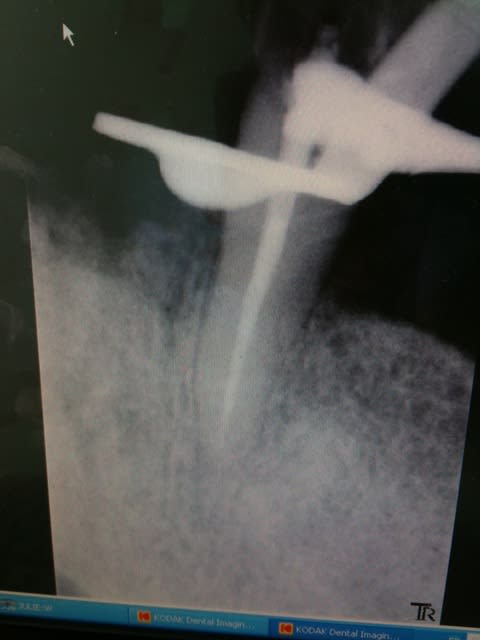

Dans le même genre......

Une patiente "basanée" et de surcroit CMU......

Qui se présente aujourd'hui avec de grosses douleurs sur cette 35............

Ca a été fait mi-juin par un de nos confrères bien connus de notre ville, même son assistante sait qu'il fait de la merde.....

En gros, le compo sur 36 (oui il en a fait un !!!) je l'ai fait sauter avec la sonde, et celui sur 35 a sauté tout seul après que je l'ai coupé en 2. Bien évidemment composite qui déborde en interdentaire....

J'ai cureté la carie dessous (qu'on ne pouvait PAS louper à moins d'être aveugle) et évidemment je suis tombé tout droit dans la pulpe......

Moralité : une CC en vue.

Sans parler de la dizaine de petites caries occlusales qu'il n'a pas vu, lui ayant dit que "tout allait bien"....

Vindiou, ptètre que j'ai pas un chiffre de la "mort qui tue" mais au moins je prends le temps de faire de la qualité......